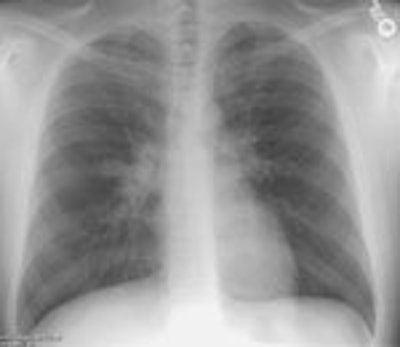

Recurrent T-cell Lymphoma in the Lungs:

(Click on the small images to view the larger radiographs)The patient shown in the radiographs below had a history of polycystic

kidney disease and gastrointestinal lymphoma. He presented with complaints

of cough. A PA chest radiograph revealed too-numerous-to-count poorly defined

pulmonary nodules.